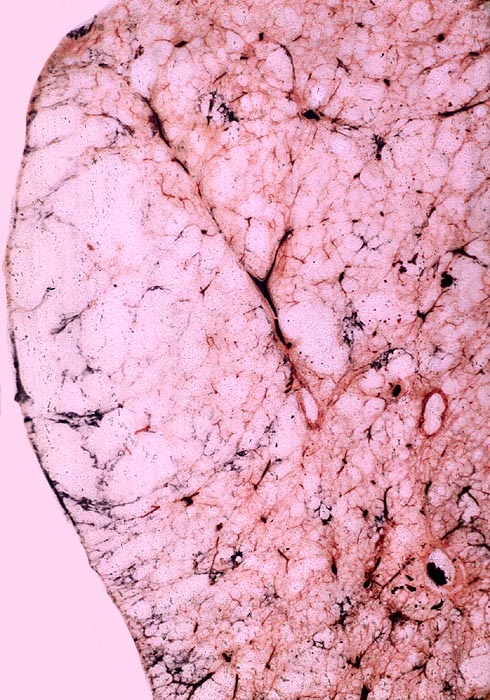

Makroskopie

Befund

Pathologischer Befund

Normalbefund